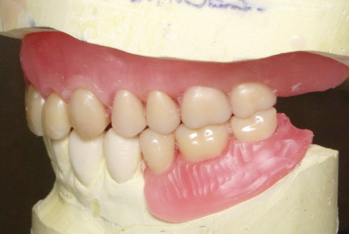

Article réservé à nos abonnés Prothèse complète numérique versus conventionnelle : à propos d’un cas clinique

En raison de l’augmentation de l’espérance de vie, le nombre de patients édentés continue d’augmenter malgré les progrès de prévention...